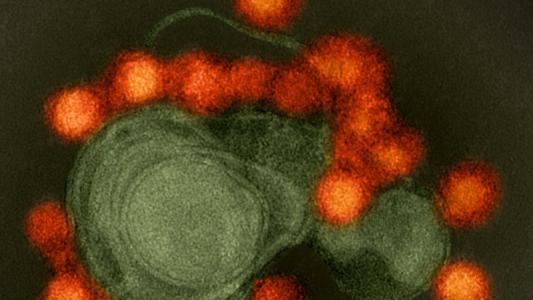

Uganda begins massive new Ebola vaccine study

The Ebola outbreak in the Congo is now the second deadliest on record. How can we stop the devastation? A study in Uganda could hold the key for a new vaccine.